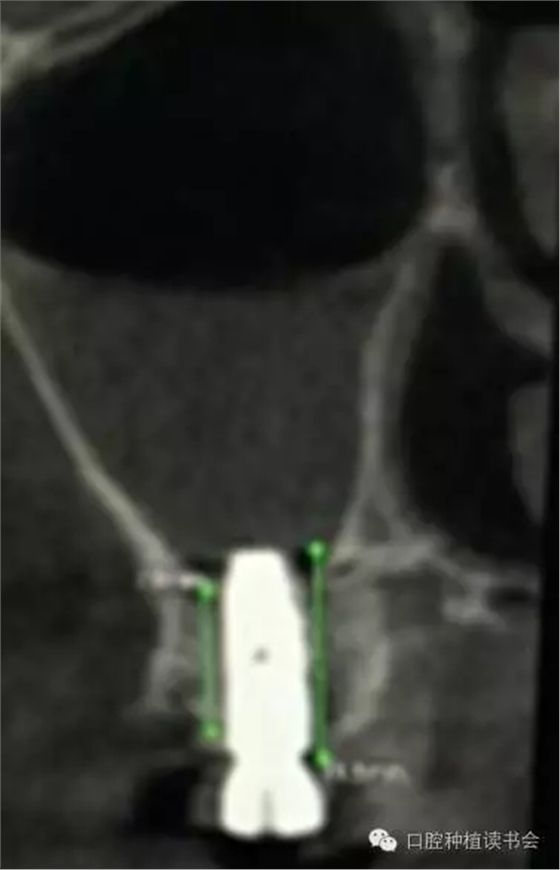

除了諸多解剖因素和生理病理因素,是否選擇上頜竇提升術(shù)(尤其是側(cè)壁開(kāi)窗術(shù))或判斷術(shù)后預(yù)期,與病人是否有基礎(chǔ)病(如糖尿病)、病人是否經(jīng)過(guò)頭部放療、是否因骨質(zhì)疏松而長(zhǎng)期服用雙膦酸鹽類藥物等相關(guān)因素均緊密相關(guān)。根據(jù)上頜竇的解剖特點(diǎn),在長(zhǎng)期實(shí)踐中,基本形成了2類上頜竇底提升的方法。1、經(jīng)牙槽脊頂提升粘膜的方法稱為內(nèi)提升,具有代表性的技術(shù)是1986年Tatum提出的經(jīng)牙槽脊提升上頜竇技術(shù)和1994年Summers提出利用內(nèi)提升器械自牙槽嵴頂入路的沖頂式上頜竇內(nèi)提升技術(shù)(osteotome sinus floor elevation,OSFE),又稱閉合式提升術(shù) (closed sinus lift technique)。前者通過(guò)牙槽脊頂切口,用特殊的窩洞成型器代替擴(kuò)孔鉆,敲擊使上頜竇底“骨折”,從而完成提升術(shù)。后者是在竇底1-2mm處用提升器進(jìn)行敲擊抬高竇底。其后多年來(lái)人們利用工具的改革創(chuàng)新,使內(nèi)提升技術(shù)有了很大的變革和進(jìn)步,如利用超聲骨刀或其他專用器械去除竇底骨質(zhì),利用球囊等工具以水、氣壓抬高上頜竇粘膜;利用環(huán)鉆進(jìn)行上頜竇底內(nèi)嵌骨塊內(nèi)提升;也有通過(guò)磁力車針進(jìn)行上頜竇底骨質(zhì)預(yù)備,通過(guò)同極排斥的原理,當(dāng)竇底骨質(zhì)去盡后,粘膜被車針“彈升”;也有通過(guò)牙槽脊頂開(kāi)窗植骨的病例報(bào)道(Winter,2003)。因此,隨著上頜竇提升技術(shù)的不斷改進(jìn)、各種新型手術(shù)器械的出現(xiàn),在RBH<4mm的情況下,上頜竇內(nèi)提升的方式也越來(lái)越被大家所采用(Nedir,2009)。2、經(jīng)側(cè)壁開(kāi)窗分離粘膜抬高竇底的方法稱為外提升(Lateral Window Technique)。早期由Philip?Boyne提出,后來(lái)上頜竇側(cè)壁開(kāi)窗在粘膜和竇底之間進(jìn)行骨增量的術(shù)式逐步應(yīng)用開(kāi)來(lái)。側(cè)壁開(kāi)窗后是否同期植入種植體,根據(jù)RBH,種植體穩(wěn)定性的預(yù)判而決定??偟膩?lái)說(shuō),上頜竇外提升術(shù)的成功率86%~100%(Jensen,2009)。根據(jù)CBCT圖像,不但可以提供術(shù)前的種植計(jì)劃指導(dǎo),而且上頜竇外提升術(shù)后的效果,尤其是檢查種植體腭側(cè)是否有植骨不全,都會(huì)一目了然。(圖10-12)